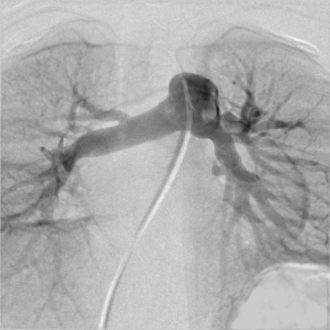

MAPCA症例 4本のMAPCAが有する症例

肺動脈統合術(unifocalizaton)術後 矢印の部分が狭窄病変

術後5ヵ月で肺動脈の狭窄に対してカテーテル治療を行った後の血管造影